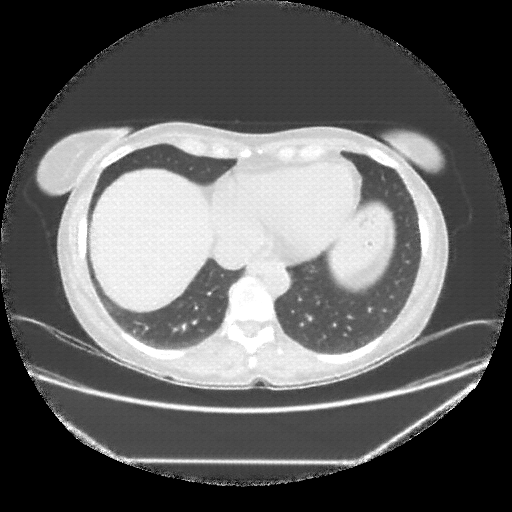

Original NATIVE CT scan (input)

No window - Raw intensity values

Lung window (WL -600, WW 1500 β†’ Low βˆ’1350, High +150)

Mediastinum window (WL 40, WW 400 β†’ Low βˆ’160, High +240)